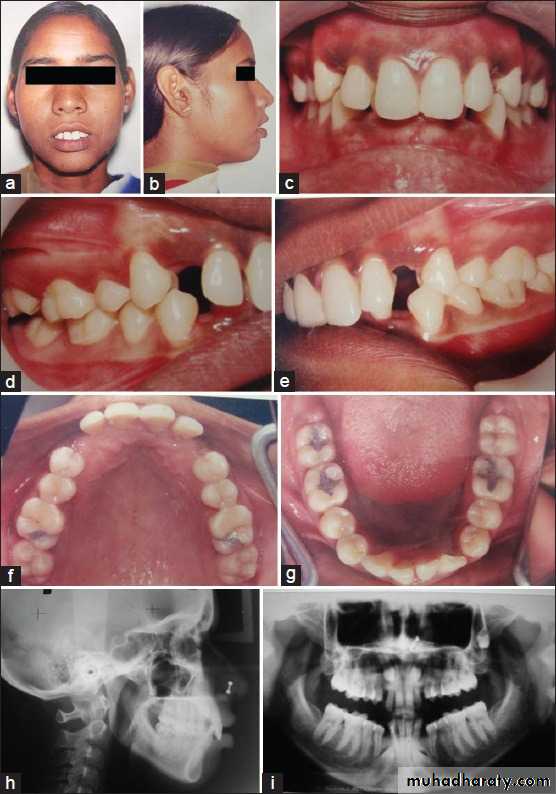

Surgical exposure :the path of eruption is not obstructed

Surgical exposure with orthodontic traction: the path of eruption is obstructed

Surgical exposure with orthodontic treatment (palatal approach )